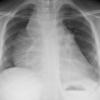

Silhouette sign

RML collapse